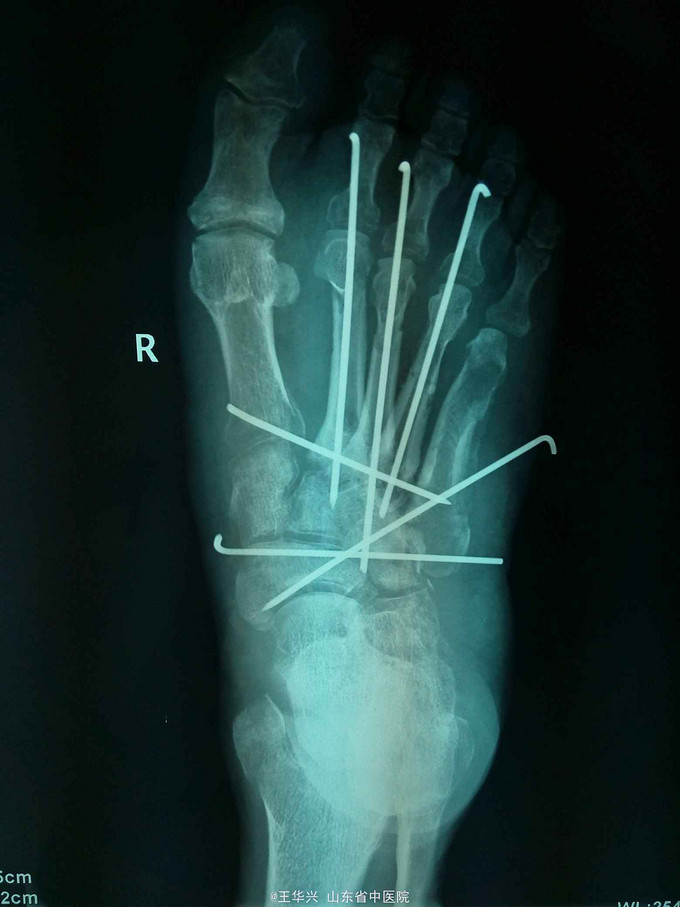

诊断:左足毁损伤 治疗:入院时已达到截肢标准,但患者家属不能接受,遂行常规手术。多次清创,行急症手术,给予简单钛针固定,软组织损伤给予原位缝合。细菌培养结果,万古霉素敏感,万古霉素局部填塞创口换药,术后给予多次清创,清除坏死组织及vsd负压吸引。待左足缺损区软组织条件可,行交腿皮瓣。

随访:现患者术后6个月,基本情况稳定,左足前部可见一软组织缺损区。 讨论:开放性外伤,行急症手术,清创要彻底,以免引起厌氧菌感染,多次清创+vsd负压吸引,换药时清楚坏死组织同时应用敏感抗生素,对抗感染及保持软组织活力。